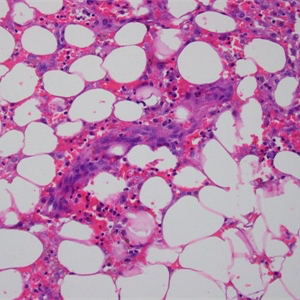

发病部位: 罕见,多位于下肢深层肌肉内;

1. 罕见,多位于下肢深层肌肉内;

2. 多结节性出血性肿物,细胞形态从梭形至上皮样不等;

4. 肿瘤性血管形态不规则,通过血窦结构互相连通,并破坏浸润周围组织,有些区域血管的肿瘤性内皮细胞过多,形成出芽、突起或乳头;